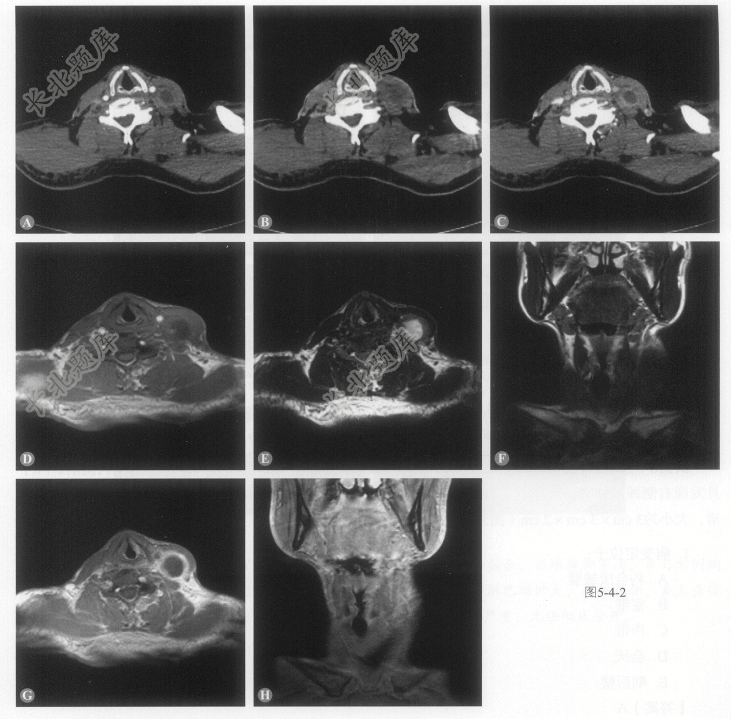

患者男性,65岁,主因声嘶1个月入院。患者于1个月无明显诱因下出现声嘶,无咽痛、呛咳,无咽异物感、干咳,无呼吸困难,无发热,就诊于医院门诊,喉镜检查:左侧声带表面凹凸不平。患者发病以来,神志清,精神可,食欲可,睡眠可,大小便正常。查体:体温:36.5℃,脉搏:76次/分,血压:152/84mmHg,呼吸:18次/分。耳鼻咽喉头颈外科查体:左侧声带表面黏膜隆起,表面不光滑。颈部可触及增大淋巴结影(图5-4-2)。

- 多项选择题1.该病例在CT增强基础上,下列哪项检查和技术更能提供定位、定性信息:

- 多项选择题2.该病变增大淋巴结位于:

- 多项选择题3.该病例淋巴结增大最常见的病因是:

- 多项选择题4.发生Ⅲ区淋巴结转移最常见的原发病灶包括:

- 多项选择题5.根据以上临床资料与CT、MRI表现特点,该病例最可能的诊断为下列哪一项: